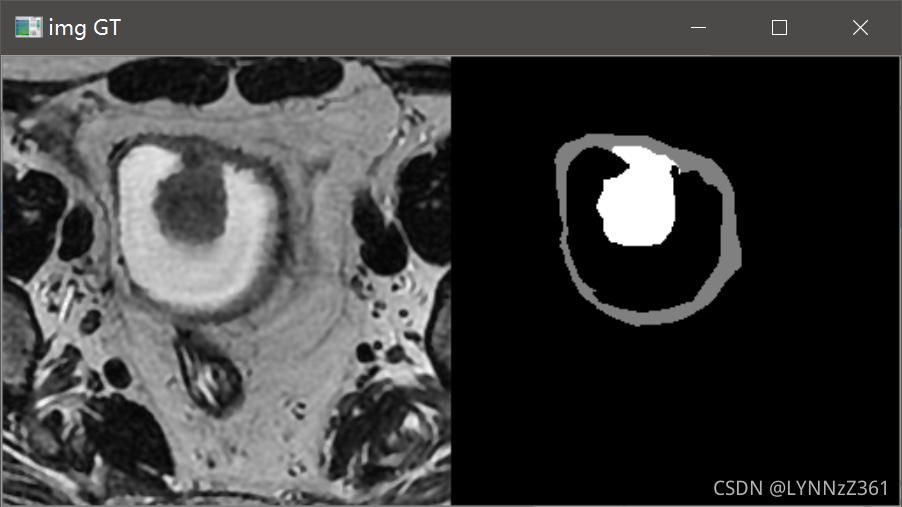

通常我会在数据预处理和加载类已写好后,运行代码测试数据的加载过程,看加载的数据是否有问题。通过可视化的结果可以看到加载的数据是正常的。

我们在对ground truth反one-hot进行可视化时,改变颜色表palette中的颜色值,就可以将ground truth重新映射成我们想要的颜色,例如:

我们修改上面的部分代码,将颜色表palette修改成三色值([x, x, x]里边有三个数字,单色[x]就对应灰色图像)将gt映射成彩色图像。